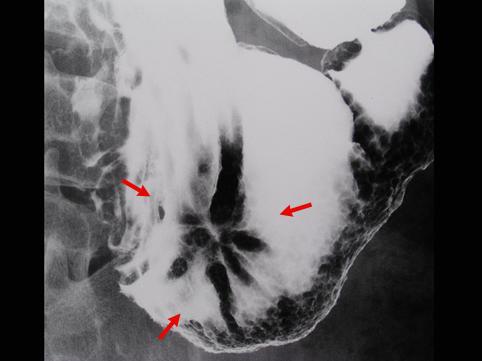

질환(병리주체)의 분류 악성 상피성종양/선암

부위(장기별) 위(부위)/위각

검사방법 X-P

종양의 육안분류 0형(표재형)/IIc형(IIc)

종양의 최대경(밀리미터) 30~34

종양의 심달도 m